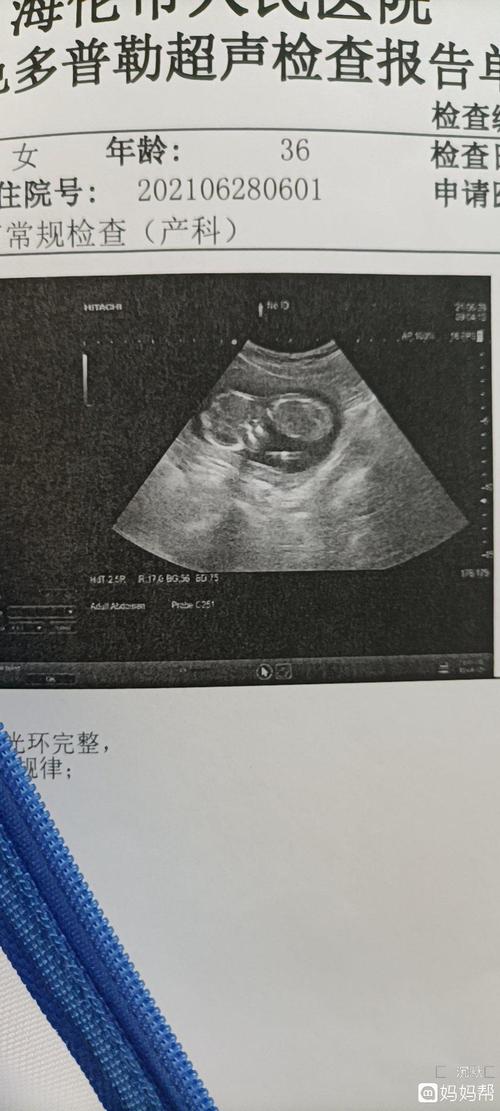

男宝彩超图片,最明显的男宝b超图

四维彩超已做,男女也知晓,大家看看是男孩

各位亲看看我刚做的四维彩超,能看出是男宝

17周家的彩超可以看出是男宝女宝吗

今天做了彩超